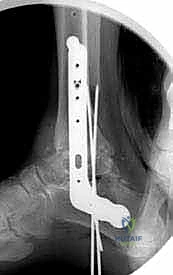

هنا تبرز الصفيحة النصلية (Blade Plate) كالحل الذهبي. تتميز هذه الصفيحة بوجود "نصل" صلب يتم إدخاله بقوة داخل عظمة الكعب، بينما يتم تثبيت الجزء الطولي من الصفيحة على عظمة قصبة الساق بالبراغي. هذا التصميم الهندسي يوفر مقاومة هائلة لقوى الانحناء والدوران، مما يضمن ثباتاً فورياً يسمح للعظام بالالتحام بشكل مثالي.

5. إدخال وتثبيت الصفيحة النصلية (Blade Plate)

هنا تكمن المهارة الجراحية الفائقة. يتم تشكيل مجرى دقيق داخل عظمة الكعب باستخدام إزميل خاص، ثم يتم طرق "نصل" الصفيحة المعدنية بحذر شديد داخل عظمة الكعب لضمان أقصى درجات الثبات.

6. التثبيت النهائي بالبراغي (Screw Fixation)

بعد التأكد من الموضع المثالي للصفيحة والنصل، يتم تثبيت الجزء العلوي من الصفيحة على عظمة قصبة الساق باستخدام براغي قشرية (Cortical Screws) قوية. يتم وضع العظام تحت ضغط ميكانيكي (Compression) لتحفيز الخلايا العظمية على الالتحام السريع.